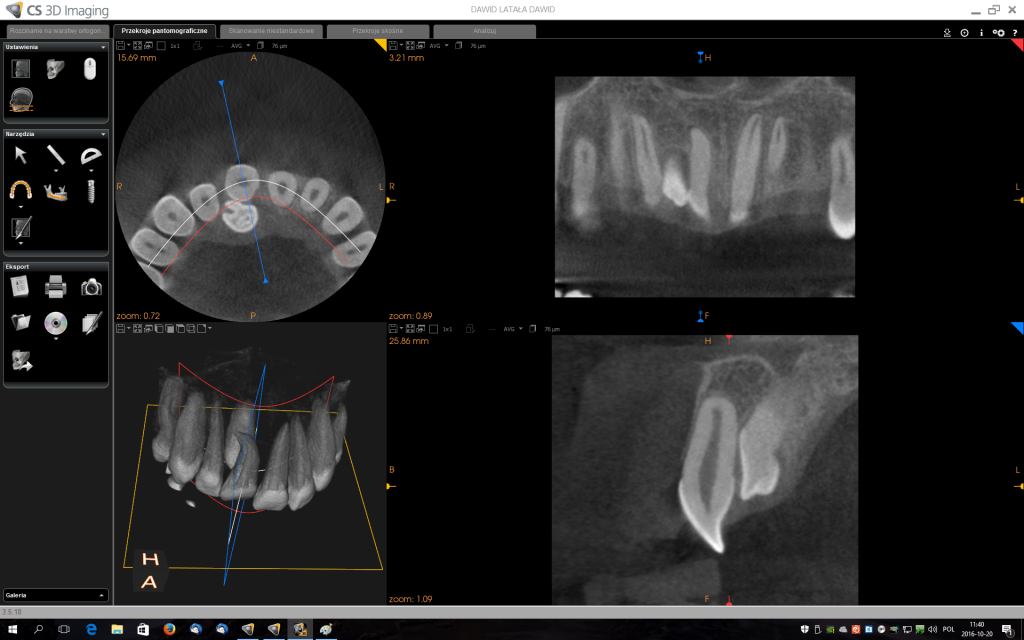

Z uwagi na moją specjalizację kierowani są do mnie pacjenci z tzw. zębami mądrości – ósemkami, które ze względu na ułożenie w kości wymagają operacyjnego usunięcia. Zdarzają się również pacjenci z mezjodensami (fot. 1,2) zębami nadliczbowymi np. dziewiątkami (fot.3), zębami zatrzymanymi (fot 4.), lub zębami zrośniętymi (fot. 5,6). Stomatolog z długą praktyką nie raz w swojej karierze zetknął się z takimi przypadkami.